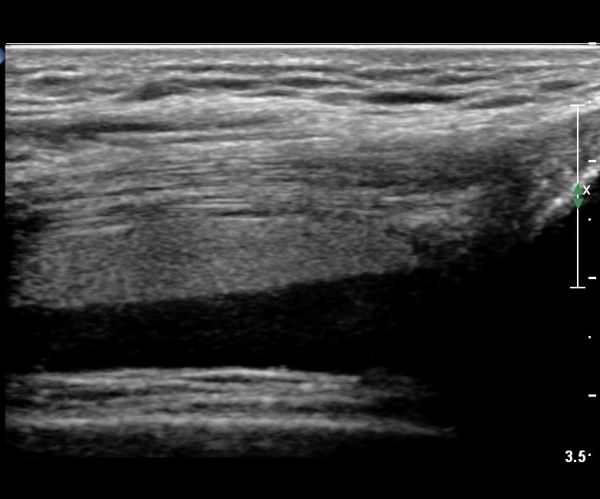

¹«¸­ Àü¸éºÎ Á¾´Ü¸é°Ë»ç¿¡¼­ °üÀý³» ¼ö¾×Àú·ù°¡ °üÂûµÇ´Âµ¥ ¼ö¾×Àú·ù Ç¥Ãþ¿¡ °í¿¡ÄÚ Áö¹æÃþÀÌ °üÂûµÊ(»çÁø 2, 3)

¹«¸­ Àü¸éºÎ Ⱦ´Ü¸é°Ë»ç¿¡¼­ °üÀý³» ¼ö¾×Àú·ù°¡ °üÂûµÇ´Âµ¥ ¼ö¾×Àú·ù Ç¥Ãþ¿¡ °í¿¡ÄÚ Áö¹æÃþÀÌ °üÂûµÊ(»çÁø 4, 5)